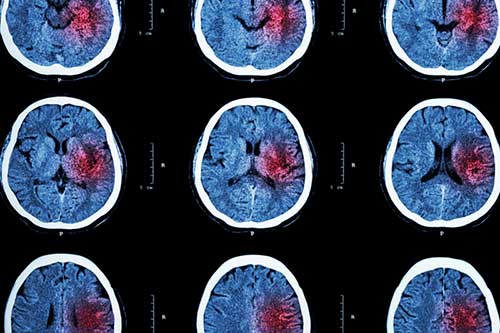

This is a wrongful death claim in which the decedent, 74 years old, was admitted to the hospital for evaluation of a two-day history of nausea and vomiting following knee surgery. She was admitted to the medical floor for observation with a diagnosis of gastritis versus upper GI bleed. An EKG had been ordered for the decedent prior to her admission, which the machine read as atrial fibrillation with rapid ventricular response. A subsequent cardiologist confirmed this reading.

The decedent suffered a stroke on 4/21/14 and required long-term assistive living until her death.